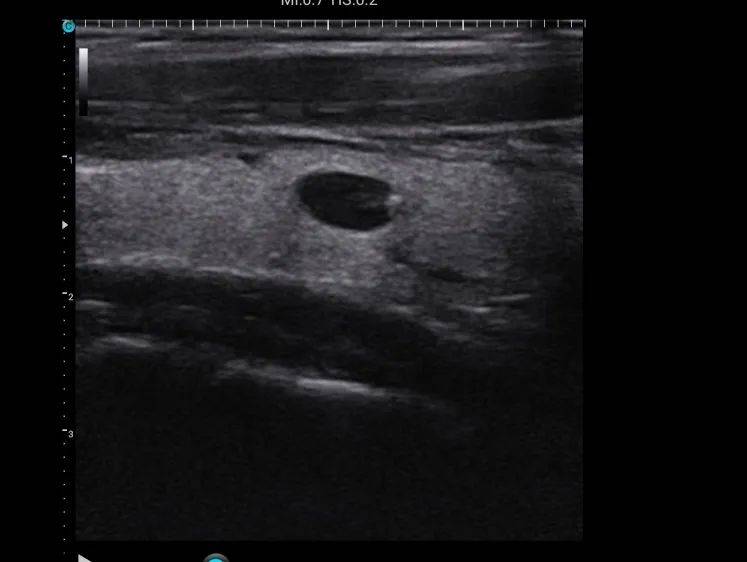

甲状腺结节超声图像解读?

对于已经发现甲状腺结节或怀疑甲状腺结节的患者,超声检查是首选的检查方法。

正常甲状腺超声图像和甲状腺结节超图像